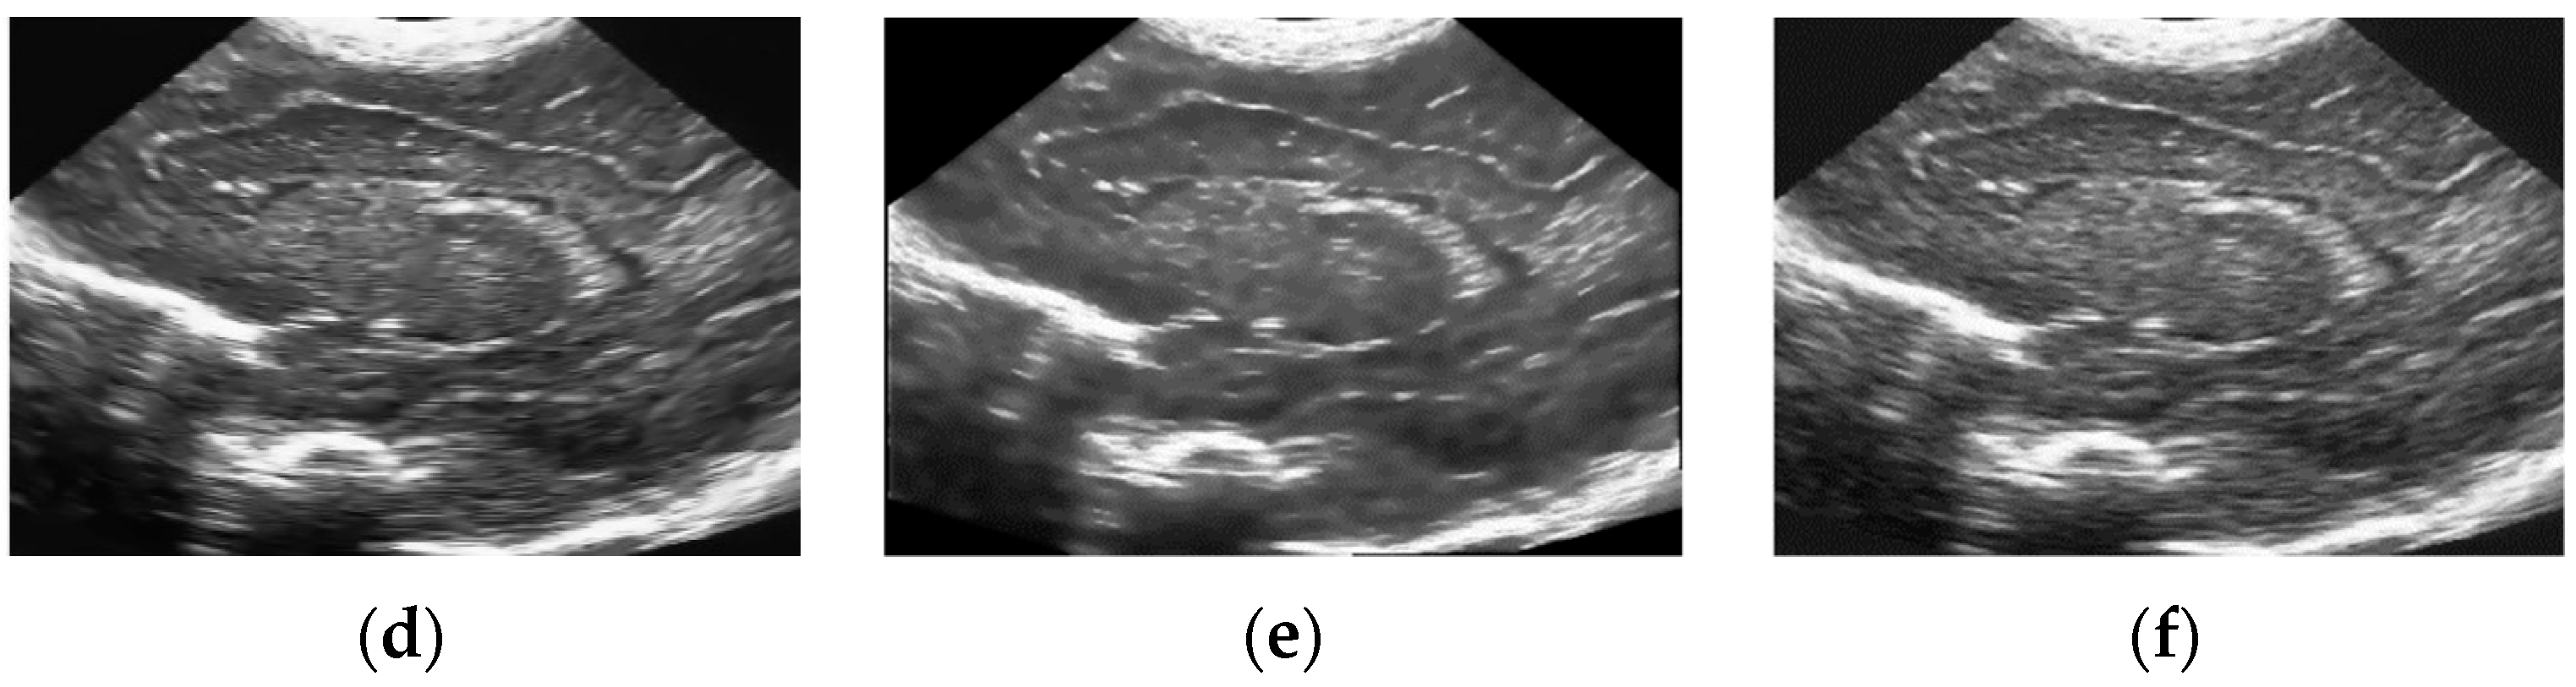

5.2. Real Ultrasound Image Denoising Experiment

5.2.2. Experimental Results